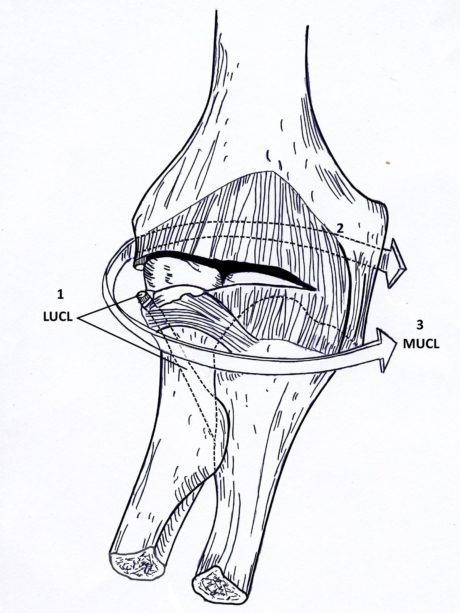

Sværhedsgraden af PLRI kan inddeles i tre faser(Camp et al. 2017):

1. Løsrivelse eller overrivning af LCL-komplekset

2. Siddende forvridning: Større anterior forskydning, progression af vævsforstyrrelser anteriort og posteriort omkring albuen til den mediale side

3. Fuld forvridning: Vævsforstyrrelse involverer det mediale kollaterale ligament, som typisk er skrællet af knoglen

Ved yderligere forskydning fortsætter forskydningskræfterne med at løsne eller rive den fælles flexor-pronator-ursprung, hvilket resulterer i en meget ustabil albue (beskrevet som stadie 3c).